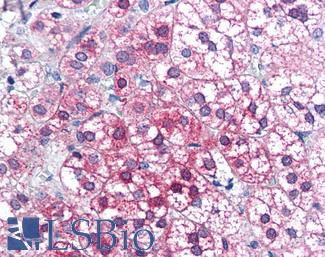

Anti-PIM1 antibody IHC of human adrenal. Immunohistochemistry of formalin-fixed, paraffin-embedded tissue after heat-induced antigen retrieval. Antibody LS-B5493 concentration 5 ug/ml.